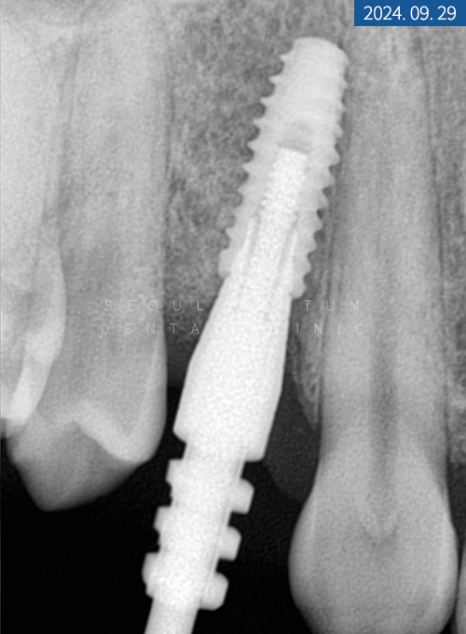

당일 #14번은 잇몸을 열고 GBR 합성골을 이식한 다음 바로 네이바이오텍 픽스처로 고정해 드렸습니다. 환자분이 1차 수술에 진행하길 원하셔서 힐링 어버트먼트로 체결해 드렸죠. 그리고 #24 좌측 소구치는 비절개를 통해 픽스처를 고정한 후 동일하게 힐링 어버트먼트로 체결해 드렸습니다. #14번 소구치는 5개월이라는 골 유착 시간을 가졌으며 #24번은 3개월이 소요되었습니다.

ISQ 장비로 인공 나사와 잇몸뼈가 잘 붙었는지 수치를 체크한 다음 정상 기준에 들어와서 힐링 어버트먼트를 제거하고 코핑을 연결했습니다. 그런 뒤 맞춤 지대주와 크라운 제작을 위해 인상 체득을 하고 다시 힐링 어버트먼트로 연결하게 되었습니다.

2주 후 기공소에서 제작된 커스텀 지대주와 크라운을 수복해 드리면서 마무리했는데요. 치근단 사진을 찍어보니 픽스처 주위에 염증 없이 단단하고 견고하게 고정되었습니다.